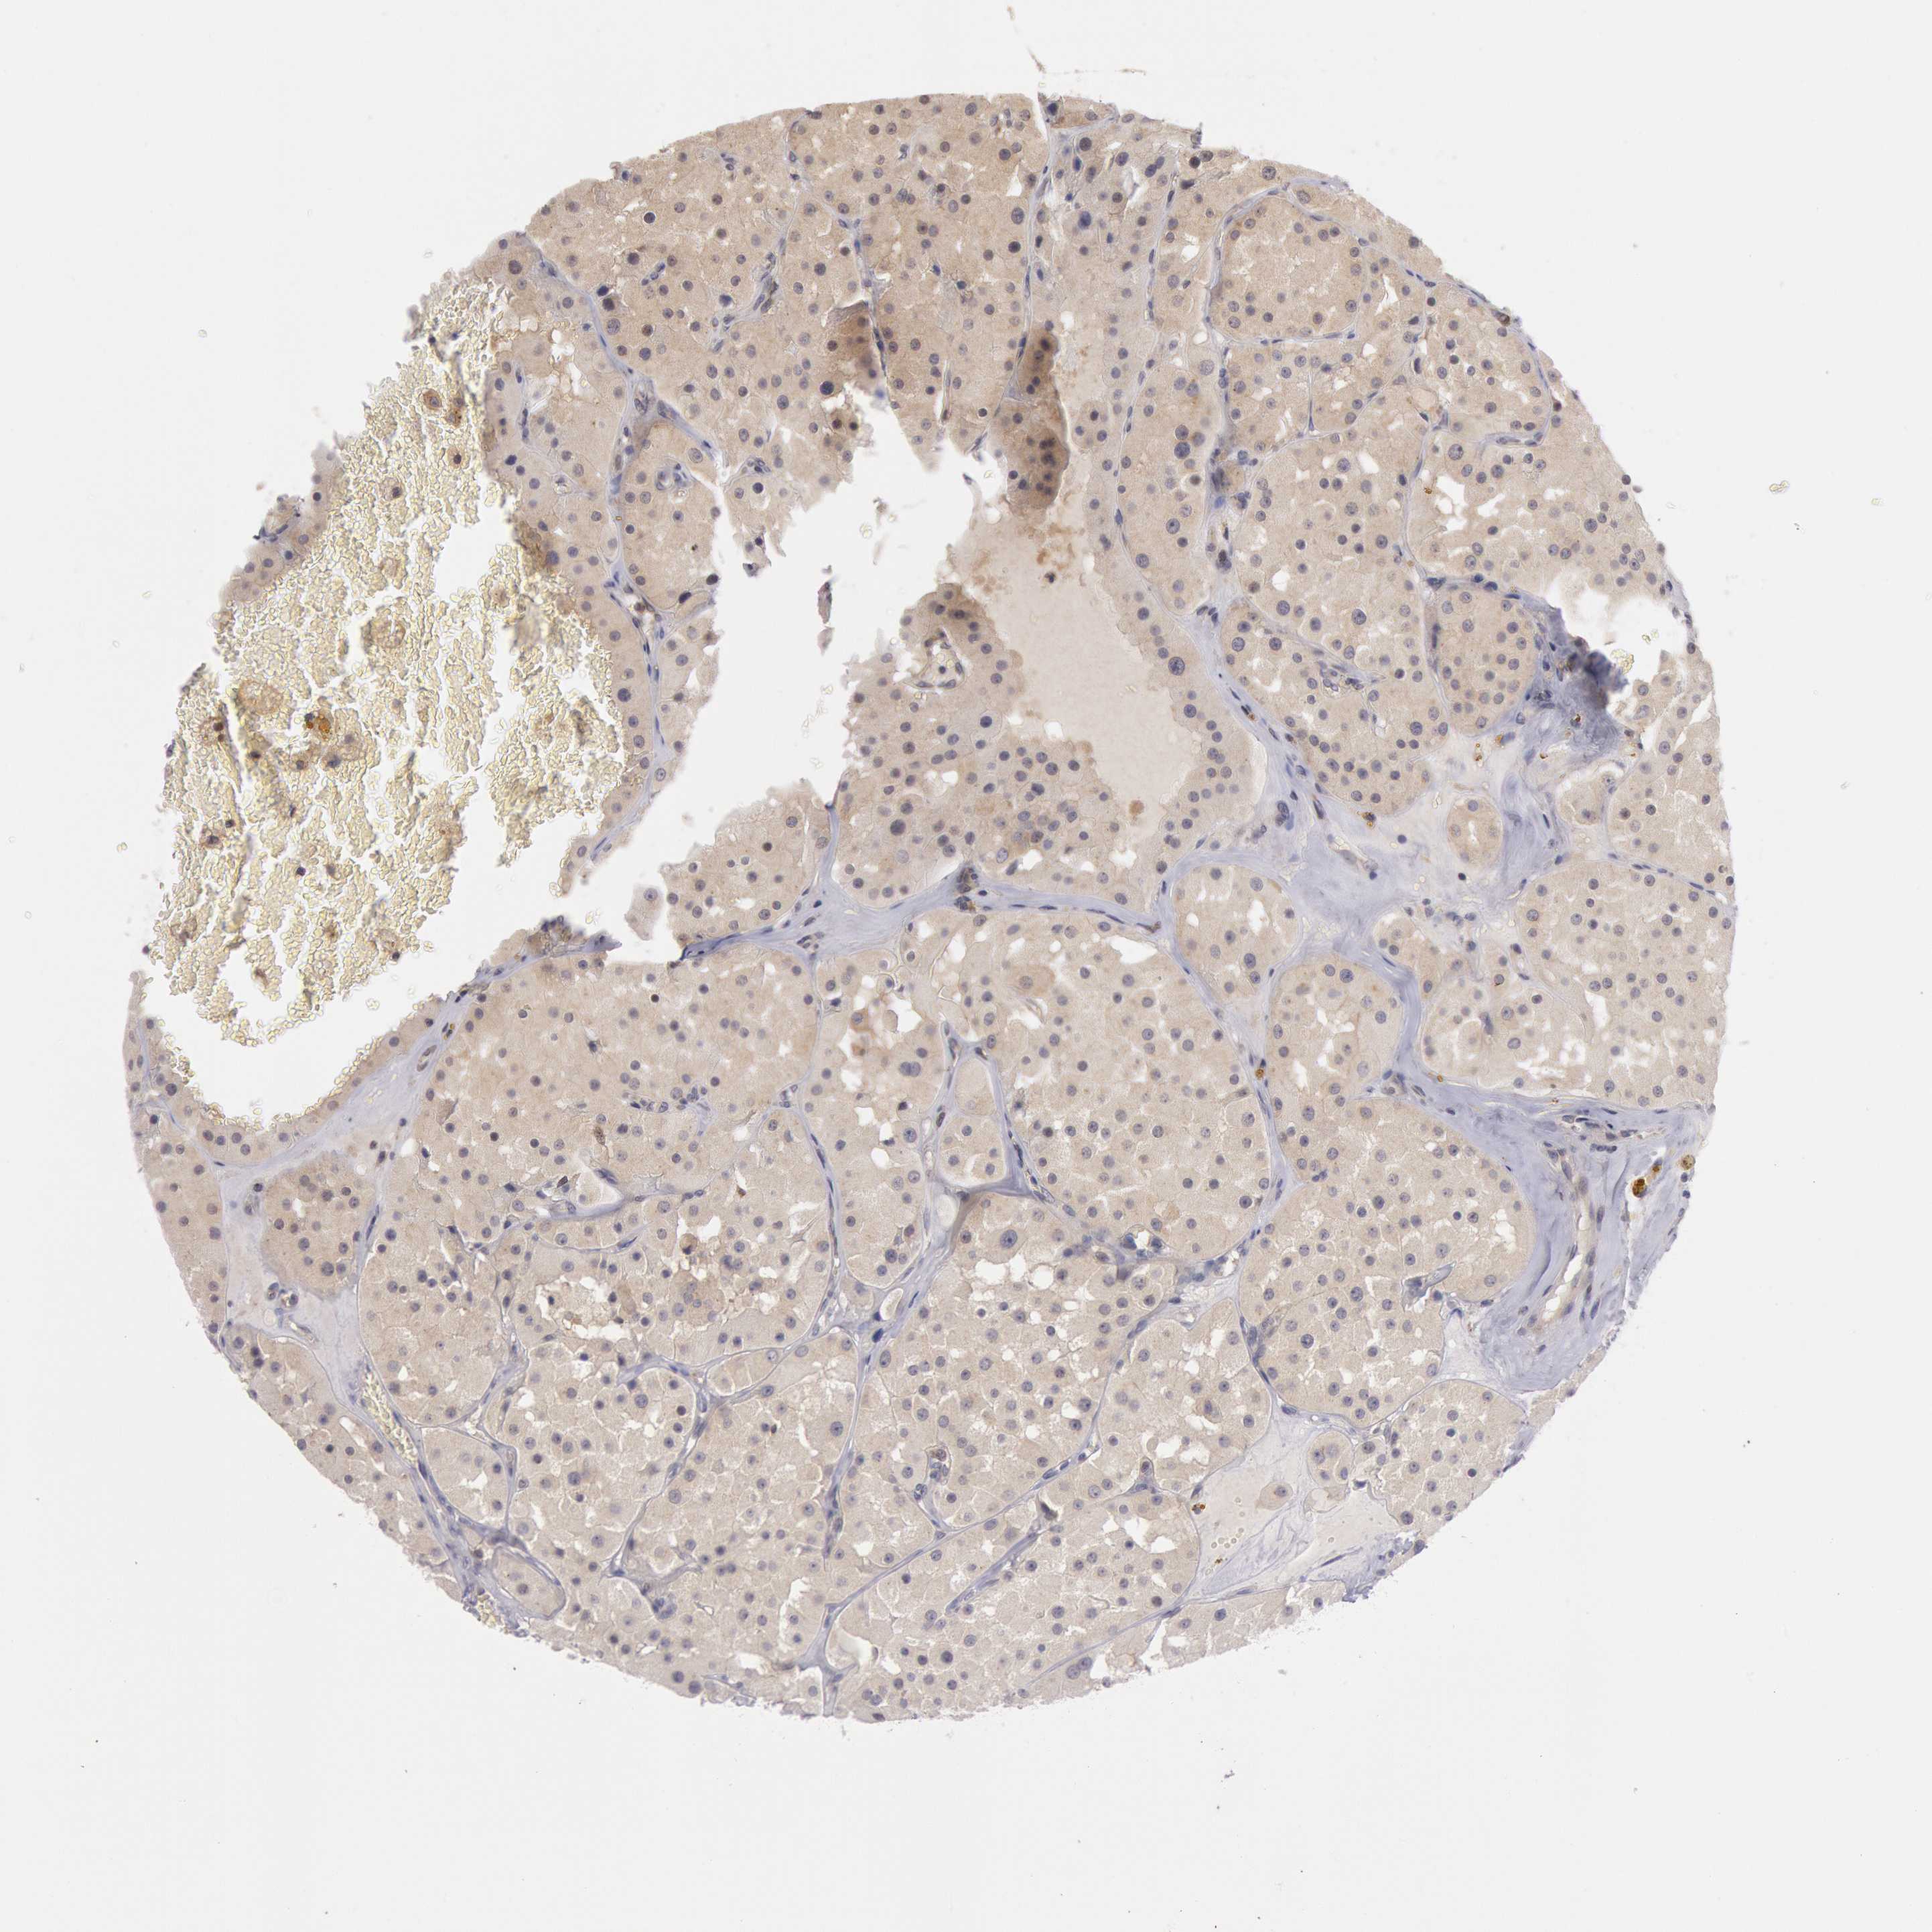

KIDNEY RENAL CLEAR CELL CARCINOMA (VALIDATION) - Interactive survival scatter ploti

The Survival Scatter plot shows the clinical status (i.e. dead or alive) for all individuals in the patient cohort, based on the same data that underlies the corresponding Kaplan-Meier plots. Patients that are alive at last time for follow-up are shown in blue and patients who have died during the study are shown in red.

The x-axis shows the expression levels (FPKM) of the investigated gene in the tumor tissue at the time of diagnosis. The y-axis shows the follow-up time after diagnosis (years). Both axes are complimented with kernel density curves demonstrating the data density over the axes. The top density plot shows the expression levels (FPKM) distribution among dead (red) and alive patients (blue). The right density plot shows the data density of the survived years of dead patients with high and low expression levels respectively, stratified using the cutoff indicated by the vertical dashed line through the Survival Scatter plot. This cutoff is automatically defined based on the FPKM cutoff that minimizes the p-score. The cutoff can be changed by dragging the vertical line or by entering a cutoff value in the square labeled "Current cut-off".

Under the Survival Scatter plot the p-score landscape (black curve; left axis) is shown together with dead median separation (red curve; right axis). Dead median separation is the difference in median mRNA expression between patients who have died with high and low expression, respectively. It is calculated as follows: median FPKM expression of dead patients with high expression - median FPKM expression of dead patients with low expression. This is intended to aid the user in visually exploring custom cutoffs and the associated p-scores and dead median separation.

Individual patient data is displayed and can be filtered by clicking on one or more of the category buttons on the top of the page. Categories describing expression level and patient information include: high, low, alive, dead, female, male and tumor stages. The scale of the x-axis can be toggled between linear and log-scale by clicking on the "x log" button. Mouse-over function shows TCGA ID, patient information and mRNA expression (FPKM) for each patient.

& Survival analysisi

Kaplan-Meier plots summarize results from analysis of correlation between mRNA expression level and patient survival. Patients were divided based on level of expression into one of the two groups "low" (under cut off) or "high" (over cut off). X-axis shows time for survival (years) and y-axis shows the probability of survival, where 1.0 corresponds to 100 percent.

PLA2G6 is not prognostic in Kidney Renal Clear Cell Carcinoma (validation)

Best expression cut offi

Based on the FPKM value of each gene, patients were classified into two groups and association between prognosis (survival) and gene expression (FPKM) was examined. The best expression cut-off refers the FPKM value that yields maximal difference with regard to survival between the two groups at the lowest log-rank P-value. Best expression cut-off was selected based on survival analysis .

When clicking on this number, the vertical dashed line indicating cut-off, the interactive survival plot, and the Kaplan-Meier curve will be adjusted to show results based on the best expression cut-off.

: 8.04

P scorei

Log-rank P value for Kaplan-Meier plot showing results from analysis of correlation between mRNA expression level and patient survival.

N/A

TCGA RNA samplesi

RNA-seq data is reported as average FPKM (number Fragments Per Kilobase of exon per Million reads), generated by the The Cancer Genome Atlas (TCGA) .

Normal distribution across the dataset is visualized with box plots, shown as median and 25th and 75th percentiles. Points are displayed as outliers if they are above or below 1.5 times the interquartile range. FPKM values of the individual samples are presented next to the box plot.

Average pTPM 10.7

Number of samples 100